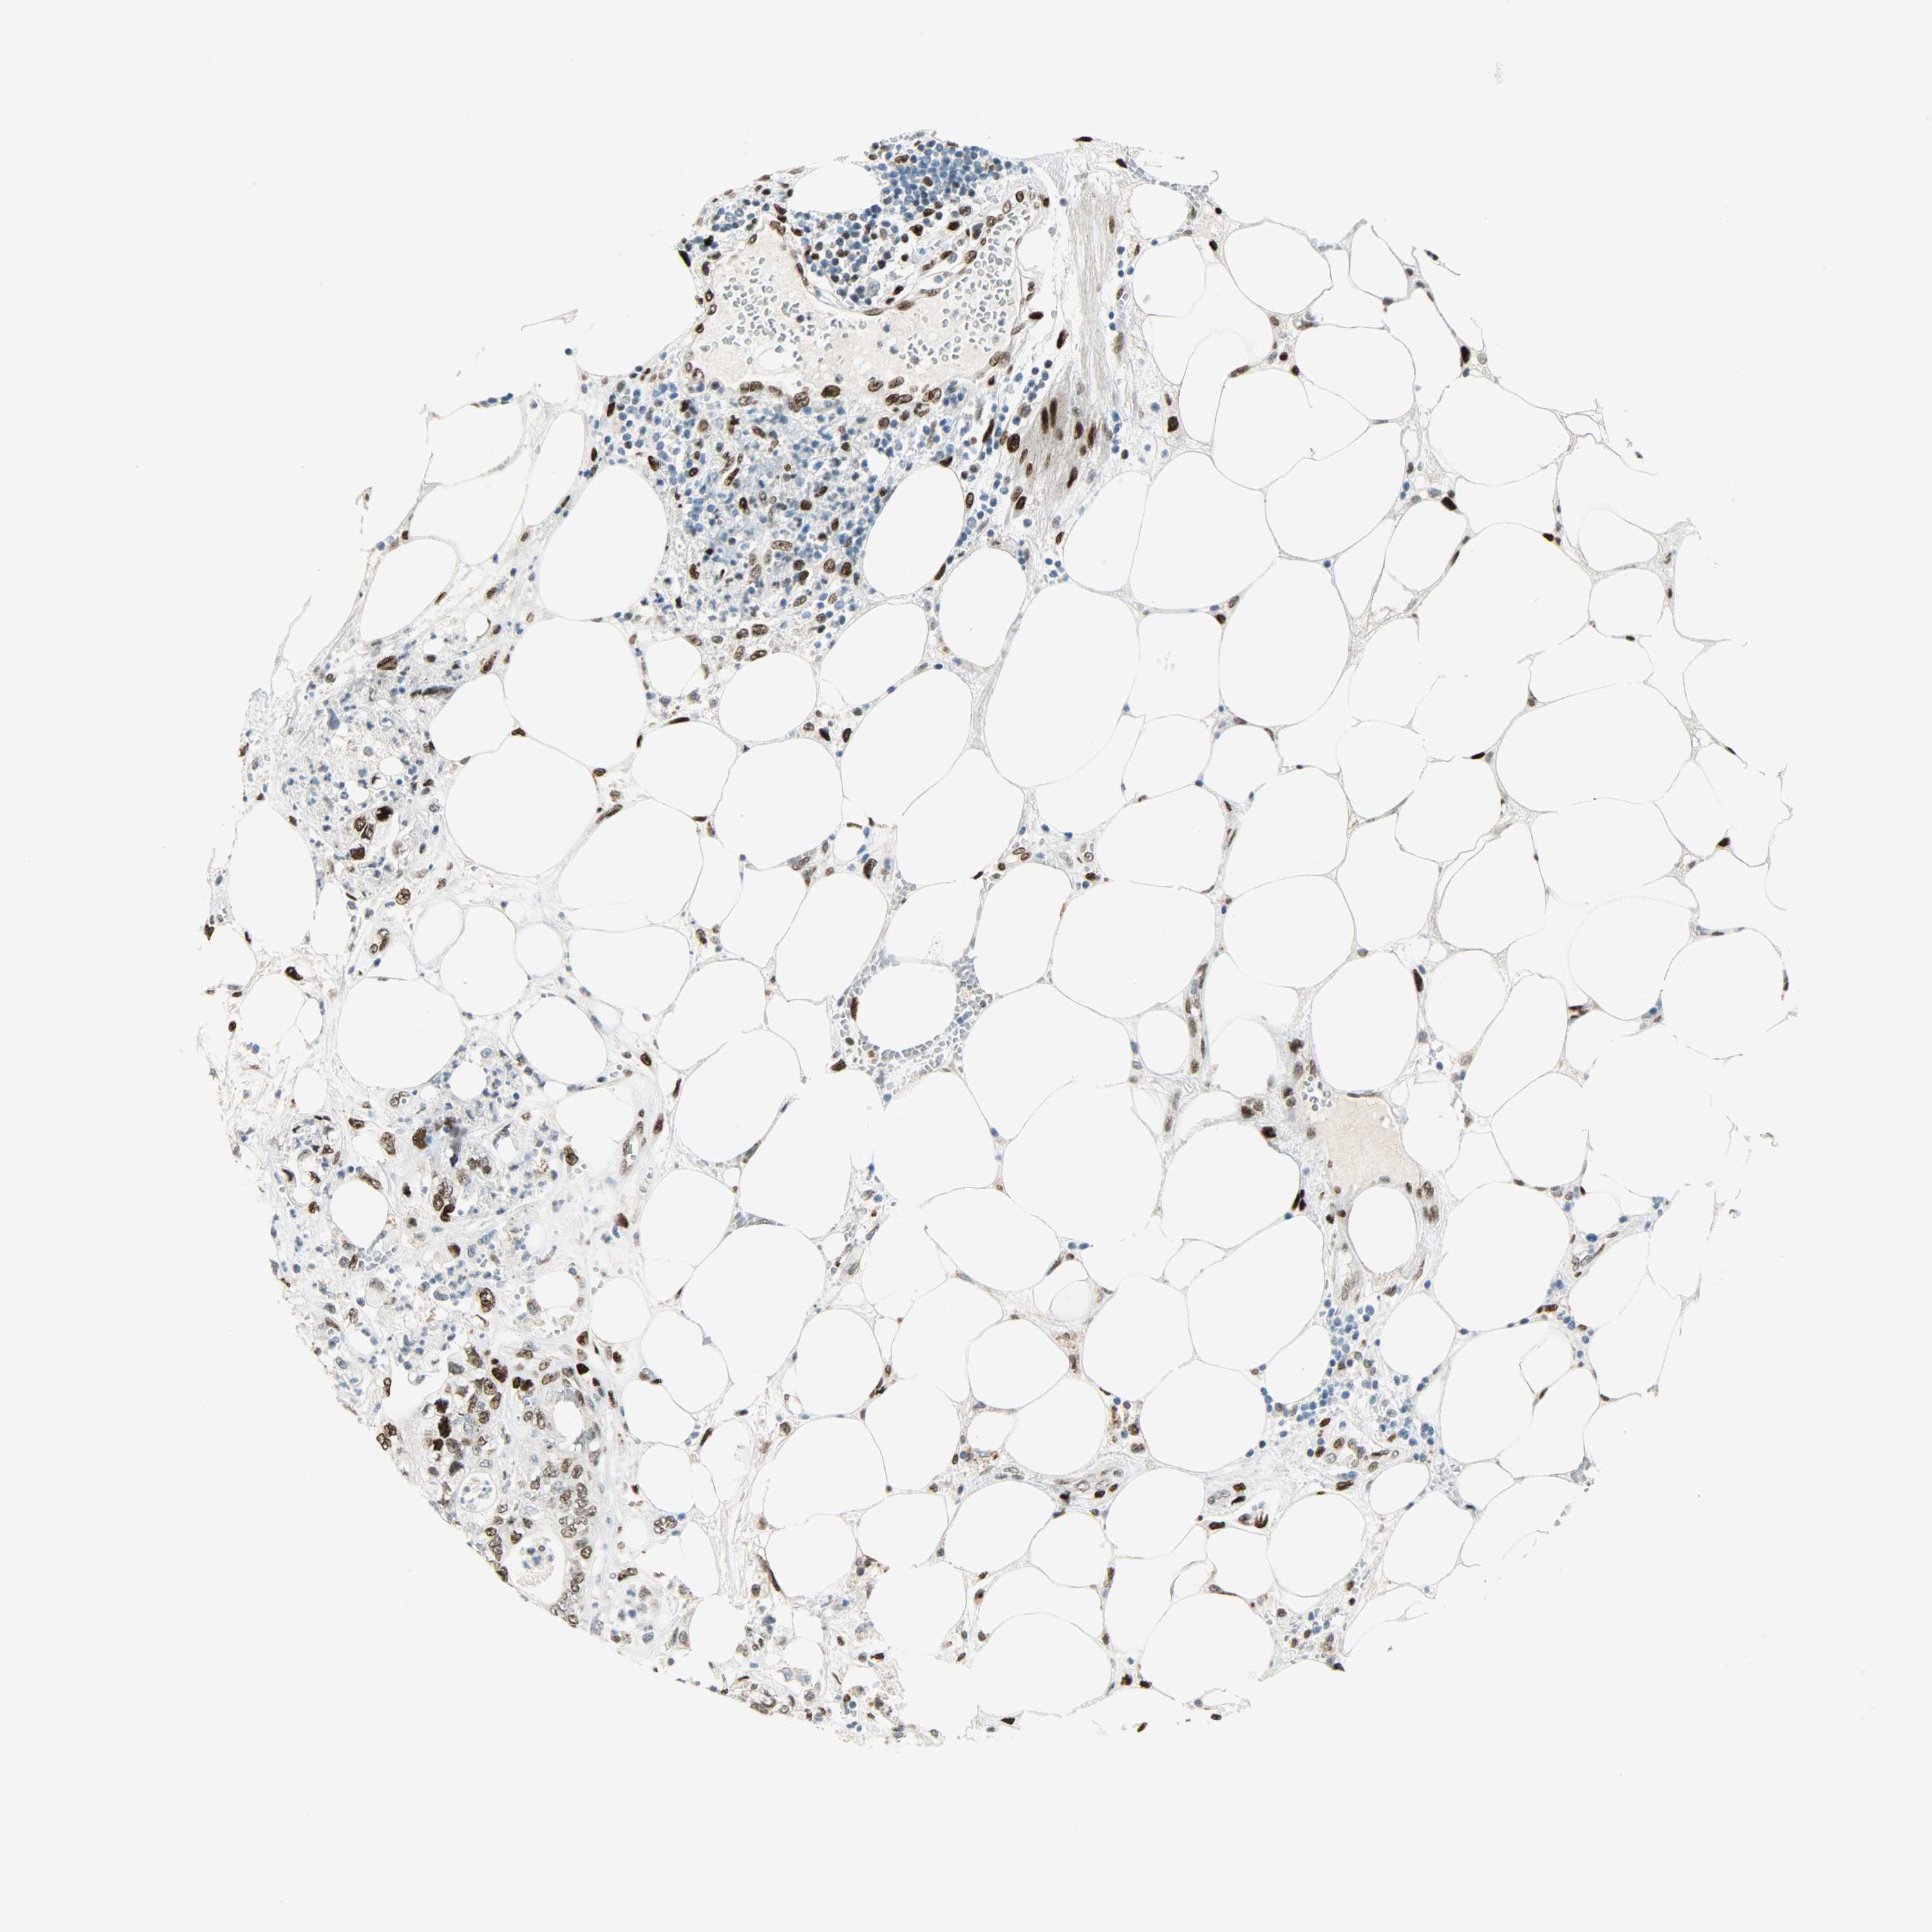

PANCREATIC CANCER - Protein expressioni

A mouse-over function shows sample information and annotation data. Click on an image to view it in a full screen mode. Samples can be filtered based on level of antibody staining by selecting one or several of the following categories: high, medium, low and not detected. The assay and annotation is described here.

Note that samples used for immunohistochemistry by the Human Protein Atlas do not correspond to samples in the TCGA dataset.

Antibody stainingi

Antibody staining in the annotated cell types in the current human tissue is reported as not detected, low, medium, or high, based on conventional immunohistochemistry profiling in selected tissues. This score is based on the combination of the staining intensity and fraction of stained cells.

Each image is clickable and will lead to virtual microscopy that enables deeper exploration of all samples and also displays staining intensity scores, fraction scores and subcellular localization as well as patient and tissue information for each sample.

Antibody HPA019149

Antibody CAB004464

Staining

High

Medium

Low

Not detected

Intensity

Strong

Moderate

Weak

Negative

Quantity

>75%

75%-25%

<25%

None

Location

Nuclear

Cytoplasmic/membranous

Cytoplasmic/membranous,nuclear

Adenocarcinoma, NOS

Adenocarcinoma, metastatic, NOS